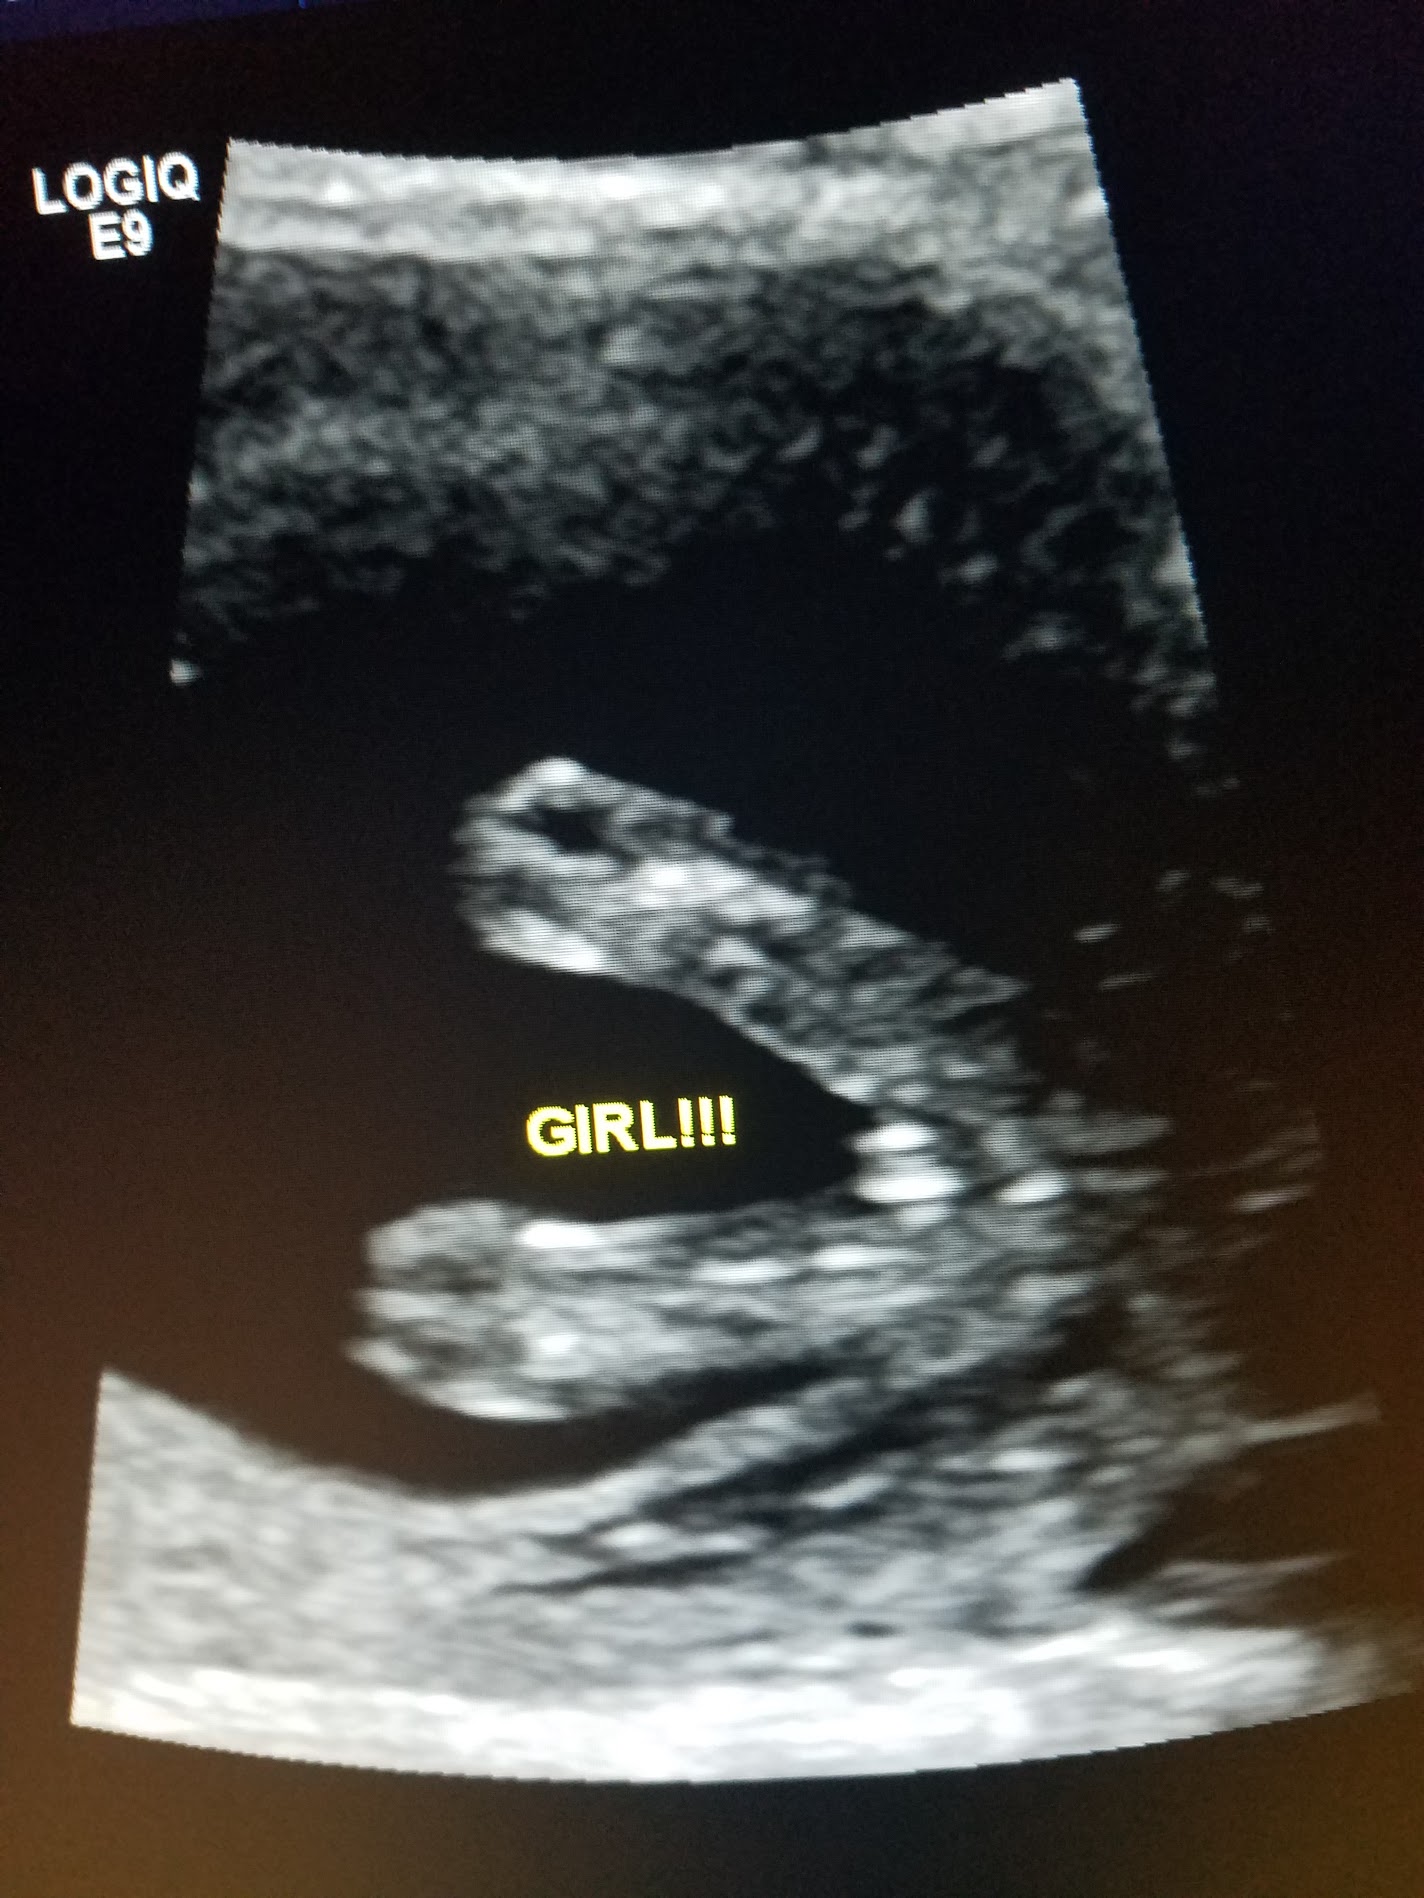

14 week 3 day potty shot...is this for sure a girl??

We went in and had my husband's coworker do an ultrasound to tell us gender yesterday and she was VERY confident that it's a girl. The ultrasound lasted for like 25 minutes and she made sure the baby was in the right position with nothing in the way and looked from multiple angles to make sure she wasn't missing anything. I just can't bring myself to believe it's really a girl (I've prepared myself forever that I'll probably only have boys so I wasn't disappointed if I didn't get a girl). Can you help me calm my nerves? This is for sure a girl right??